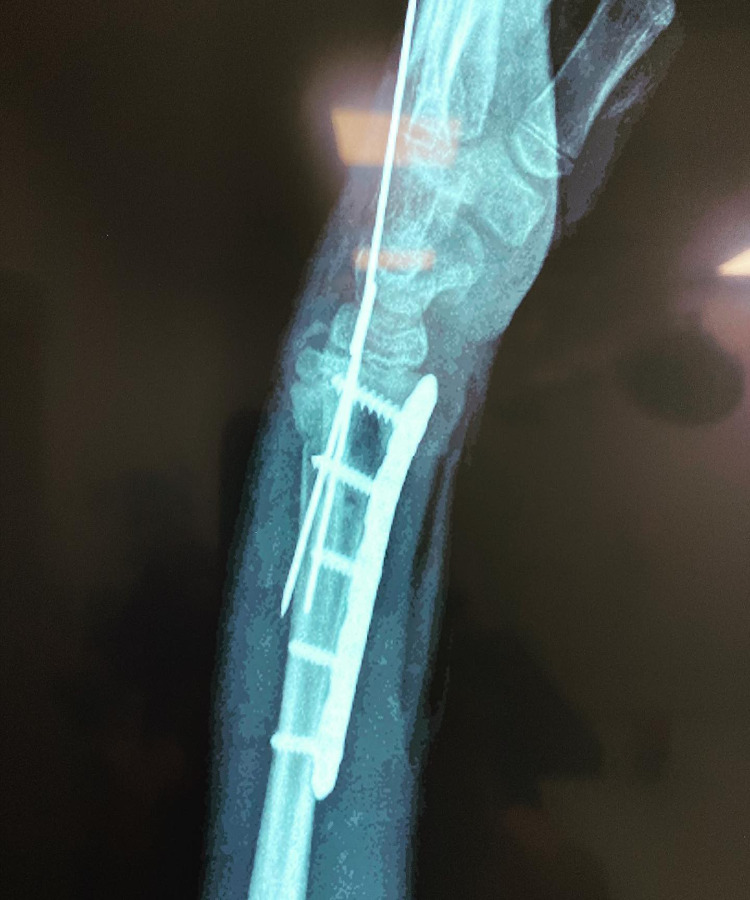

conocer másLas fracturas en niños son comunes y pueden afectar su crecimiento si no se tratan debido a las características únicas de sus huesos en desarrollo.